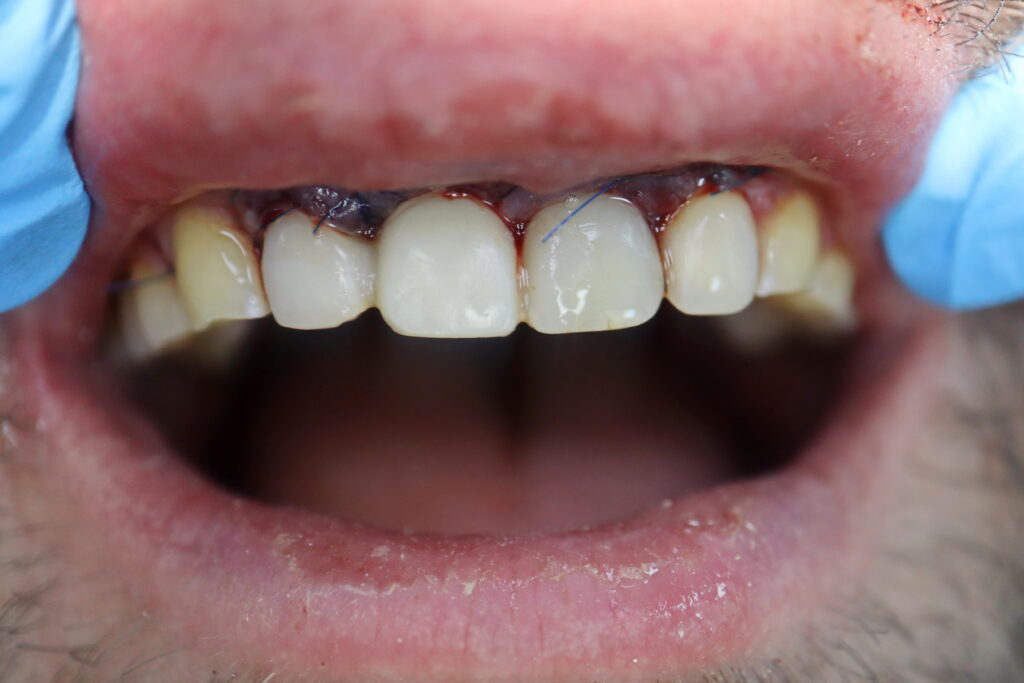

Ситуация до лечения

Диагноз: Радикулярная киста в области зуба 1.1

пациент до имплантации